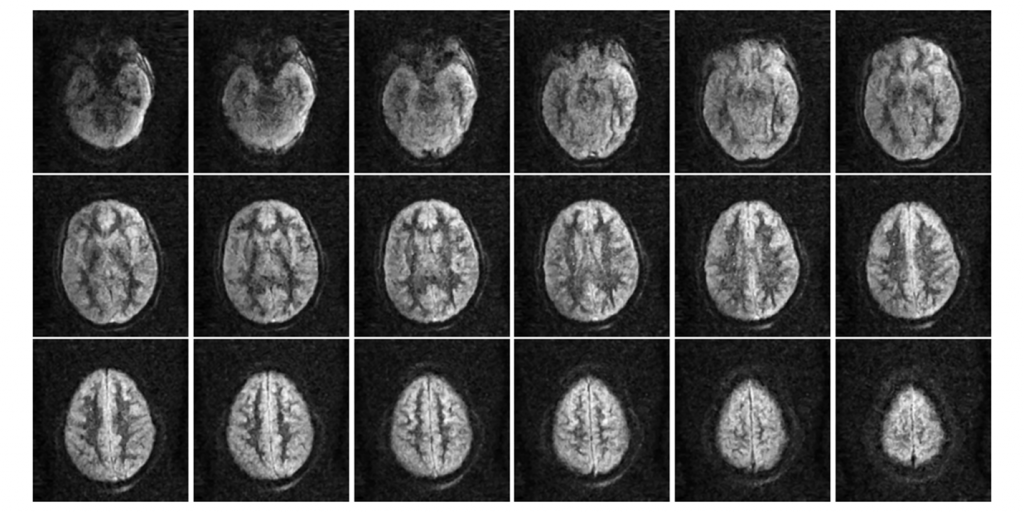

- High-Resolution Imaging

- Revolutionary Low-Field Technology Operates at just 87 mT, delivering diagnostically valuable images through advanced spatial coding algorithms.

Brain Images